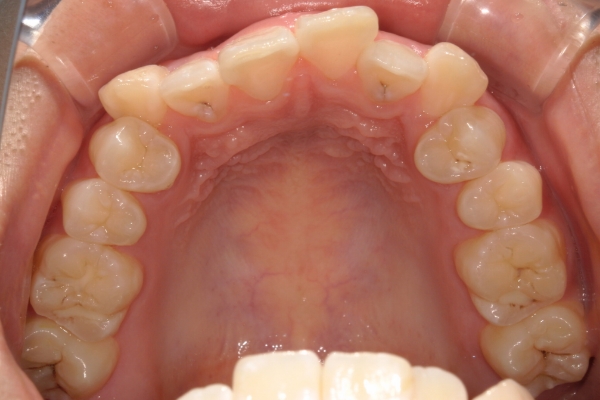

BEFORE

治療前

PROCESS

3か月

AFTER

治療後

骨格的に下あごが前下方に長いことが原因で、受け口、開咬(前歯が当たらない)の症状がでていました。また下あごが右にずれており、その影響で上下の歯列正中(真ん中)の大きなずれも生じていました。顎変形症手術も選択肢の一つでしたが、患者さまの希望もあり、下顎左側小臼歯の抜歯をして通常の歯列矯正で治療をしました。

治療後は、前歯、奥歯の噛み合わせが整い、上下の歯列の真ん中が一致しました。歯列全体のアーチも安定し、機能面・審美面のどちらも大きく改善されました。